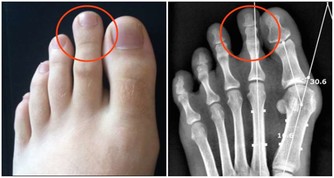

2. 指甲強韌

指甲也能很好地反映健康狀況。

就像壓力會影響你的頭髮一樣,身體緊張時指甲會出現水平狀突脊。

如果指甲紅潤、堅韌、平滑有光澤,說明你相當健康。